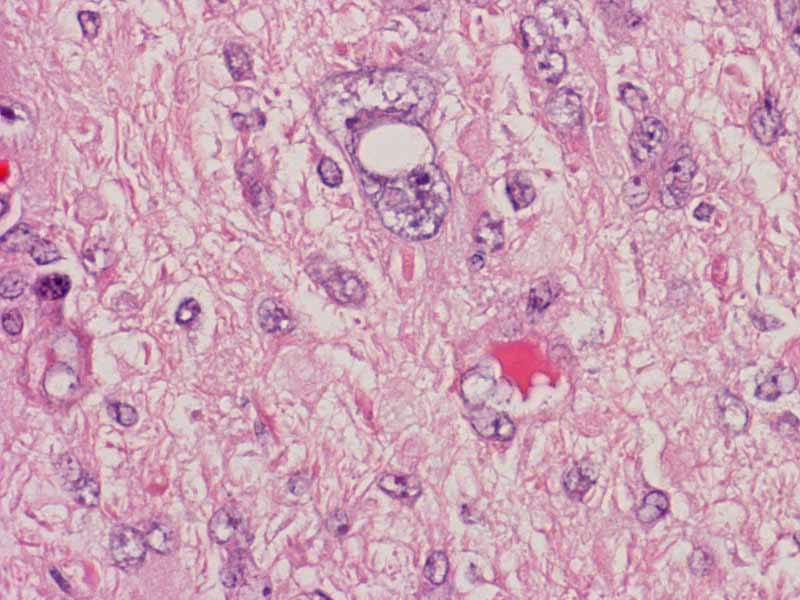

Area 1: The tumor is composed of large, pleomorphic cells with large nucleoli. The tumor cells are densely packed and without any pattern formation. The nuclei are large and there are prominent nucleoli. A moderate amount of cytoplasm is also present. The morphology varies from more spindle appearing to more epithelioid appearing.

This image is taken from another slide of this case. In this area, the rhabdoid features are more prominent. Rhabdoid changes are featured by a large nuclei with prominent nucleoli. The cells is typically in an oval shape with a large belly of cytoplasm that pushes the nucleus to an eccentric location. Within the belly of cytoplasm is often a faintly defined inclusion body like body which may appear fibrillary on hematoxylin and eosin stain. This structure is composed largely of vimentin and will be strongly highlighted by immunohistochemistry for vimentin.